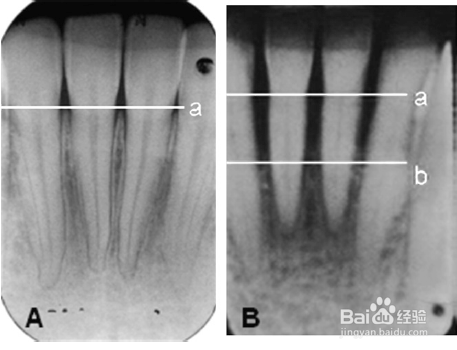

下颌前牙的X光片。图A和B中的a线所示是正常的牙槽骨高度,图B中的b线所示为牙周炎导致的牙槽骨吸收后的高度,只为正常高度的1/2。